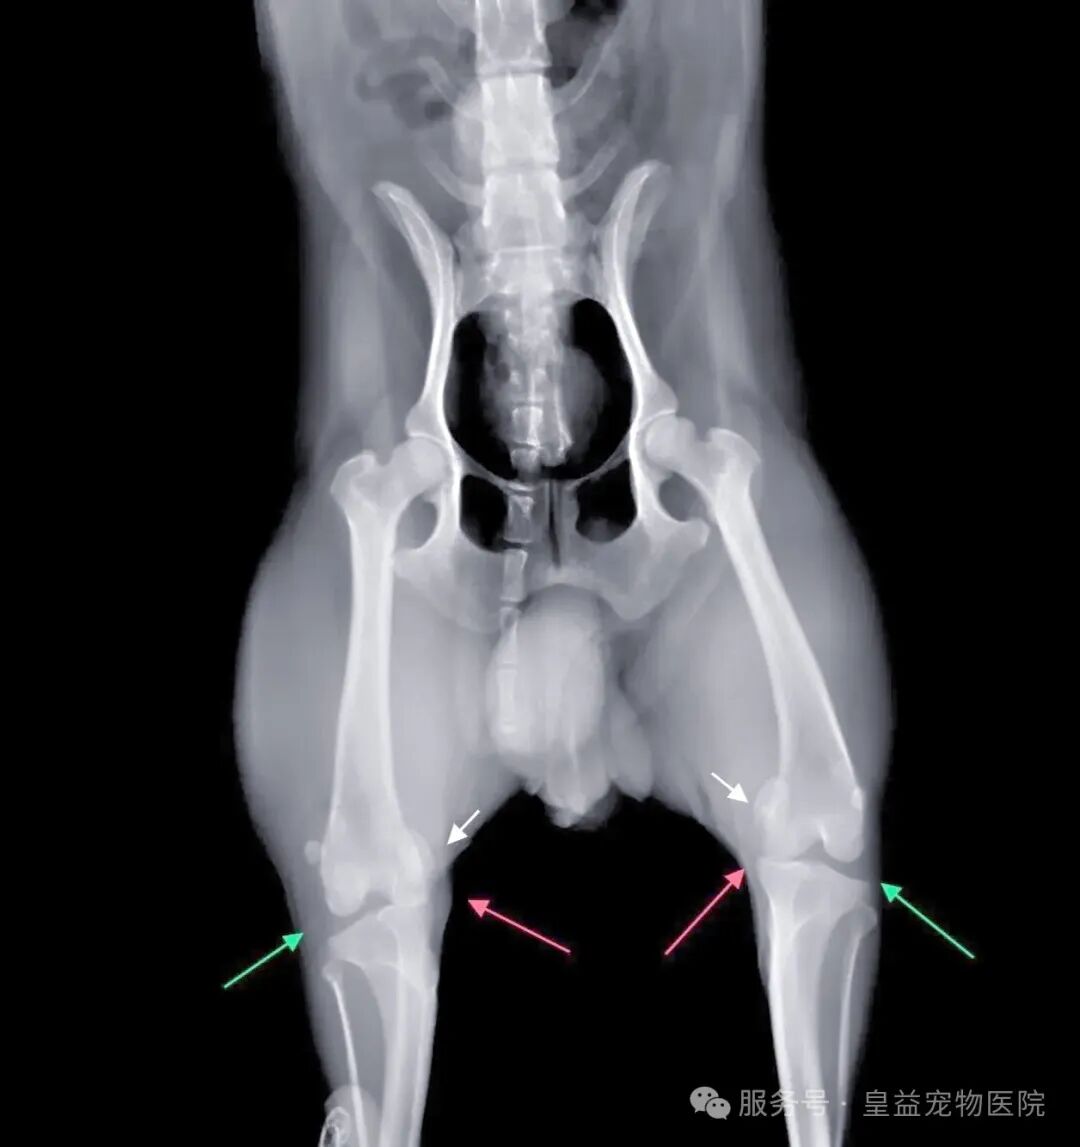

贵宾、博美、吉娃娃等小型犬携带遗传易感基因,70%病例为双侧发病。这些品种的骨骼结构存在先天缺陷:

- 滑车沟过浅(轨道太窄)

- 股骨远端畸形(轨道倾斜)

- 胫骨结节偏移(牵引力方向错误)

2. 幼犬期监控:4月龄前可拍摄X光早期干预